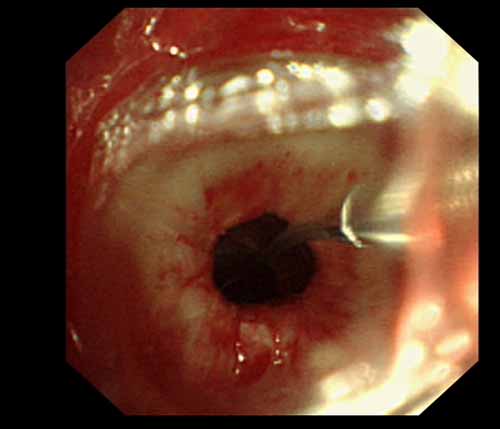

患者李某某,女,45歲,因氣管插管咳嗽、喘憋10天入院。頸部CT檢查示聲門下約20mm處氣管明顯狹窄,狹窄段長約26mm,最窄處直徑約4.4mm。支氣管鏡檢查見聲門下約2cm氣管呈漏斗狀縮窄,直徑約4-5mm,支氣管鏡無法通過。經科室討論,決定行電子支氣管鏡下氣管球囊擴張治療。與患者及家屬充分溝通并經三方見證談話簽署知情同意書后,在患者持續吸氧、局麻下,科主任于世倫主任醫師帶領治療小組為患者實行電子支氣管鏡下氣管球囊擴張術。手術過程順利,出血量很少,術后患者呼吸困難癥狀即可明顯緩解。10天后行二次擴張,患者日常活動無明顯喘憋,二次術后5天出院。

術前聲門下的漏斗樣狹窄口 術中球囊擴張 術后擴張開的氣管管腔